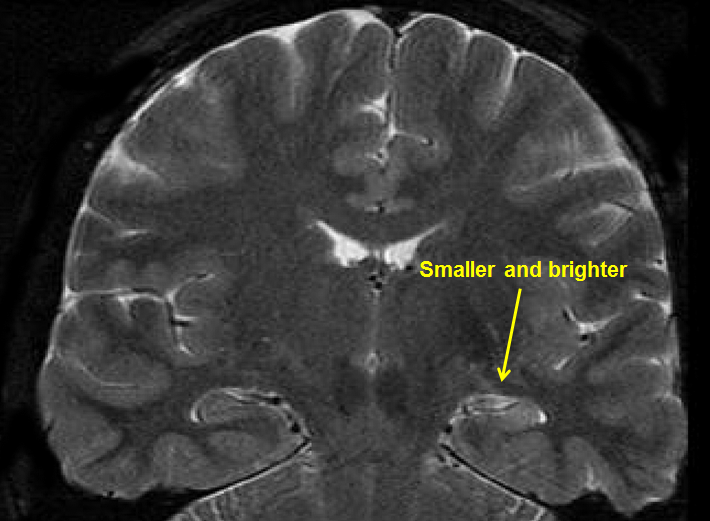

Medial TLE can be associated with hippocampal sclerosis, as shown on the MRI scan above.

Mesial temporal lobe epilepsy is often associated with changes or abnormal findings on MRI (magnetic resonance imaging). One of the most common findings is scarring in the temporal lobe. This is called hippocampal sclerosis (sclerosis means hardening or scarring). It may look like the hippocampus on one side, or both, has shrunk or is smaller.

Right Mesial Temporal Sclerosis (MTS)

Also, see arrow in figure at the top of the page.